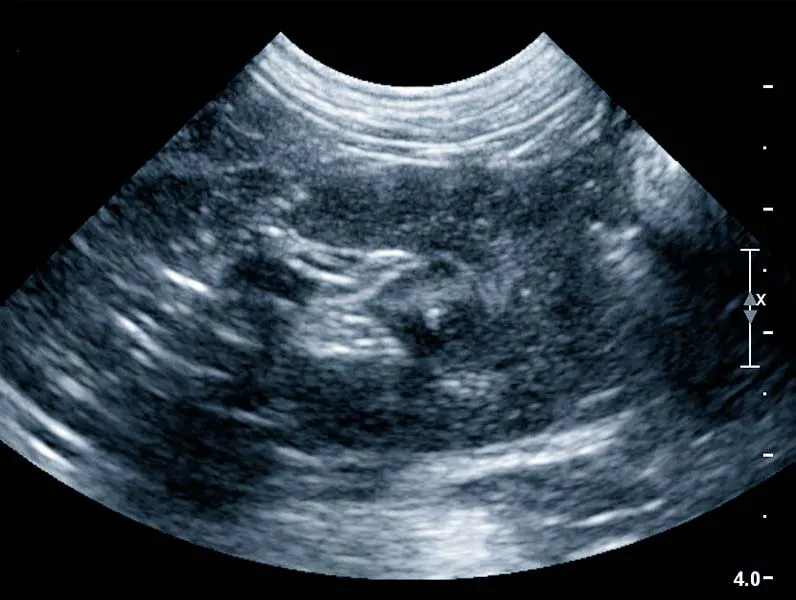

Ultrazvučna pretraga je važan dijagnostički alat u veterinarskoj medicini jer omogućuje veterinarima da dobiju detaljan uvid u unutarnje strukture tijela bez potrebe za invazivnim postupcima.

Tijekom ultrazvučne pretrage dio tijela je izložen bezopasnim, visokofrekventnim zvučnim valovima kako bi stvorio slike unutarnjih struktura tijela na ekranu uređaja.

Tako uživo možemo vidjeti kretanje, funkciju i strukturu unutarnjih organa vašeg ljubimca.

UZV se koristi u svrhu dijagnostike bolesti svih organa trbušne šupljine, srca i krvožilnog sustava.